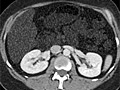

Computed Tomography (CT) Scan of the Body

A computed tomography (CT) scan uses X-rays to make detailed pictures of structures inside of the body.

During the test, you will lie on a table that is attached to the CT scanner, which is a large doughnut-shaped machine. The CT scanner sends X-rays through the body area being studied. Each rotation of the scanner provides a picture of a thin slice of the organ or area. All of the pictures are saved as a group on a computer. They also can be printed.

A CT scan can be used to study all parts of your body, such as the chest, belly, pelvis, or an arm or leg. It can take pictures of body organs, such as the liver, pancreas, intestines, kidneys, bladder, adrenal glands, lungs, and heart. It also can study blood vessels, bones, and the spinal cord.